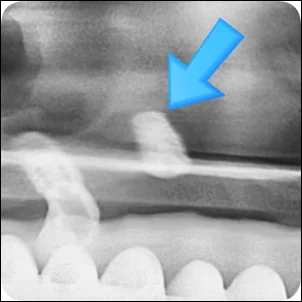

오산 재신경치료 이미 치료한 치아의 통증, 기둥이 세워진 경우 안녕하세요. 서울버팀치과 엄용국 원장입니다. 오늘은 한 환자분의 사례를 소개해 보려고 합니다. 신경치료를 받았던 치아에 다시 증상이 나타나 내원하신 경우였는데요. 신경치료가 끝난...